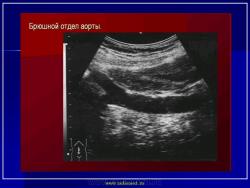

УЗИ  аорты.